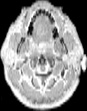

Visible Human male: Sectio transversalis 1171

NMR

Pd T1 T2